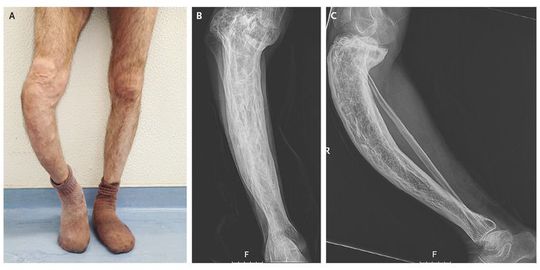

A 57-year-old man presented with long-standing, painful deformation of the right tibia. He reported increased volume of the right leg since late adolescence and three low-impact fractures in the fourth decade of life. He was treated 15 years before presentation with calcitonin for 6 months, without symptomatic relief. Physical examination revealed a prominent saber-like tibia and superficial venous circulation related to chronic venous insufficiency (Panel A). Radiographs showed cortical thickening, trabecular enlargement, and bowing of the tibia (Panel B shows the anteroposterior view and Panel C the lateral view). Levels of bone turnover markers were increased, including an alkaline phosphatase level of 345 U per liter (normal range, 45 to 129), an N-terminal propeptide of type I procollagen (P1NP) level of 506.3 ng per milliliter (normal value, <36.4), and a level of the β-isomer of the C-terminal telopeptide of type I collagen (β-CTX) of 1.38 ng per milliliter (normal value, <0.30). These findings show the clinical sequelae of prolonged early-onset Paget's disease of bone. Zoledronate at a single dose of 5 mg was prescribed owing to the increased metabolic activity in a weight-bearing location. Near-normalization of the alkaline phosphatase level (69 U per liter), the P1NP level (40.6 ng per milliliter), and the β-CTX level (0.34 ng per milliliter) was seen after 1 year, with symptomatic improvement.